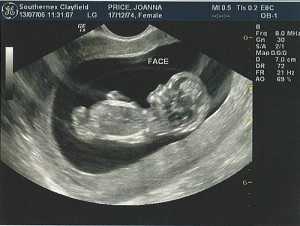

Фото плода, фото живота матери, УЗИ на сроке 11 недель

УЗИ

- Первое официальное ультразвуковое обследование проводится именно на 11 неделе. К этому времени плод подрос уже настолько, что его будет отлично видно. Так что можно оценить правильность его развития.

Что покажет УЗИ на 11 неделе беременности

Обычно на этом сроке делают УЗИ, на котором можно услышать, как у малыша бьется сердце, увидеть, как он шевелится. Первое УЗИ на 11 неделе беременности обычно делают для подстраховки, для исключения каких-либо отклонений. УЗИ позволяет оценить состояние плода, плаценты, матки, и входит в скрининг первого триместра.

УЗИ — безопасное для малыша исследование, которое позволяет на ранних сроках определить наличие или отсутствие отклонений в его развитии. Не стоит бояться делать УЗИ!

Фото УЗИ на 11 неделе беременности